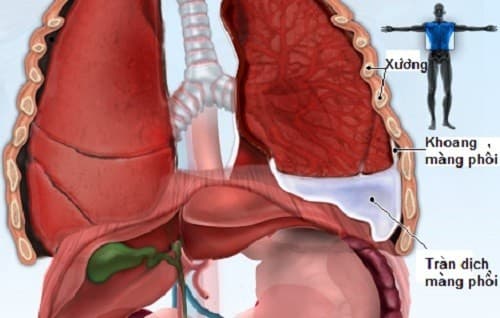

Tràn dịch màng phổi là thuật ngữ dùng để chỉ tình trạng tích tụ dịch trong khoang trống giữa phổi và thành ngực, đó là sự tích đọng dịch có thể là máu, dịch hoặc khí vượt quá mức cho phép của khoang màng phổi. Vậy tràn dịch màng phổi có nguy hiểm không Tràn […]

Tràn dịch màng phổi có thể gặp phải ở mọi lứa tuổi. Vậy tràn dịch màng phổi nguy hiểm không và làm thế nào để điều trị bệnh hiệu quả? Tràn dịch màng phổi là gì? Khoang màng phổi là một khoang ảo nằm giữa phổi và thành ngực. Bình thường nó cũng có một […]

Tràn dịch màng phổi là tình trạng tích tụ dịch trong khoang chống giữa phổi và thành ngực, đó là sự đọng dịch có thể là máu, dịch hoặc khí vượt quá mức cho phép của khoang màng phổi. Mục tiêu chính của xử lí tràn dịch màng phổi là: Lấy dịch ra, dự phòng các […]